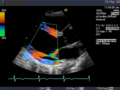

Ihre Hauptanwendung findet diese Untersuchungsmethode in der Echokardiografie, um Bewegungen einzelner Herzmuskelbereiche und der Herzklappen genauer untersuchen zu können. Die zeitliche Auflösung dieses Modus ist bestimmt durch die maximale Wiederholrate der Schallimpulse und beträgt schon bei 20 cm Tiefe über 3 kHz.

-

Anwendung des Doppler-Verfahrens bei einer Herzuntersuchung: Mitralklappeninsuffizienz -